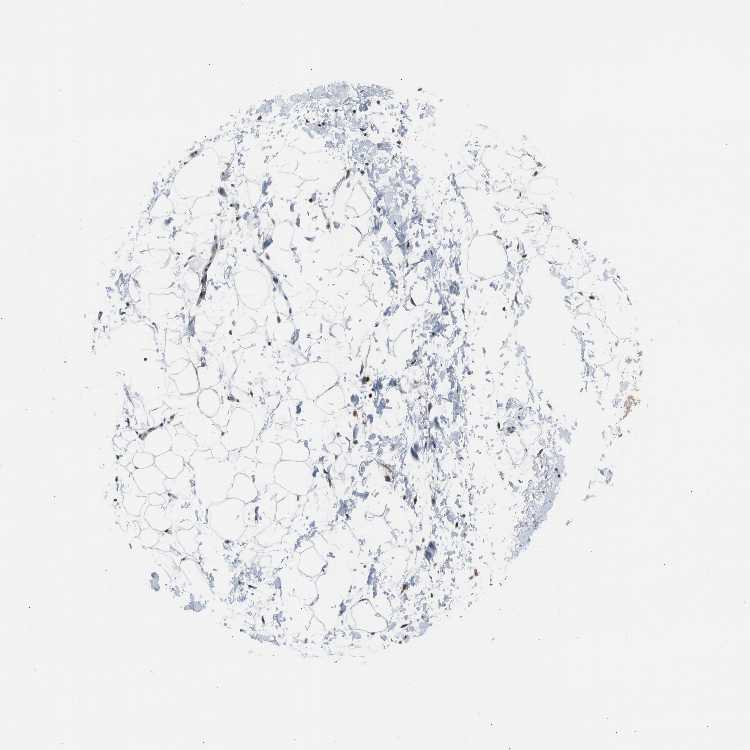

SOFT TISSUE 1 - Antibody stainingi

Antibody staining in the annotated cell types in the current human tissue is reported as not detected, low, medium, or high, based on conventional immunohistochemistry profiling in selected tissues. This score is based on the combination of the staining intensity and fraction of stained cells.

Each image is clickable and will lead to virtual microscopy that enables deeper exploration of all samples and also displays staining intensity scores, fraction scores and subcellular localization as well as patient and tissue information for each sample.

Antibody HPA006912

Fibroblasts Medium